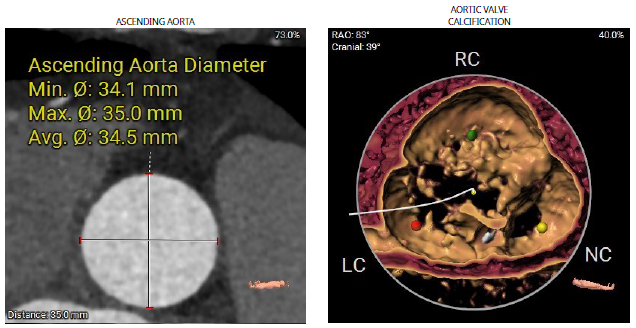

2023年2月10日,重庆医科大学附属第二医院殷跃辉、苏立教授团队联合医院麻醉、超声、放射等多学科团队,成功应用Evolut PRO TAVR系统治疗一名主动脉瓣中度狭窄伴重度关闭不全患者。该病例瓣叶单边增厚,中度主狭伴重度反流,且冠状动脉粥样硬化,阻塞风险高;术者认为介入瓣膜的多次稳定回收性,对手术的成功起至关重要的作用。

患者为76岁女性,因“反复喘累半月”入院。心脏彩超显示,左房、左室增大,升主动脉增宽,肺动脉增宽。收缩期主动脉瓣口流速350cm/s,平均压差:27mmHg,最大压差49mmHg,舒张期主动脉瓣口左室侧见大量红色为主的花色血流信号,速度438cm/s;EF 48%。诊断主动脉瓣中度狭窄伴重度关闭不全、左房、左室增大、心包积液(少量)、左室收缩功能降低、二尖瓣重度关闭不全、三尖瓣轻度关闭不全。既往患有高血压。